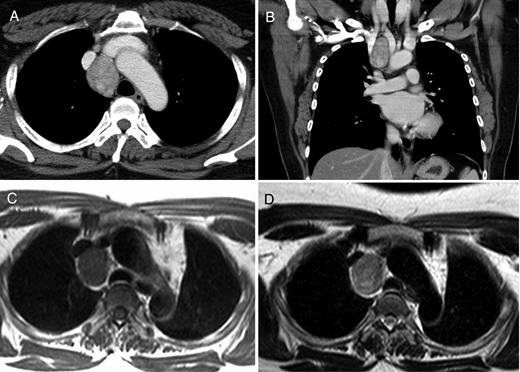

Contrast-enhanced CT revealed a heterogeneous tumor measuring 4 cm in the middle mediastinum. The tumor was surrounded by many mediastinal structures, including brachiocephalic trunk, right brachiocephalic vein, superior vena cava (SVC), azygos vein, ascending aorta and trachea. However, its invasion to these mediastinal structures was uncertain (Fig. 1A and B). By magnetic resonance imaging (MRI), the tumor showed low intensity on both T1- and T2-weighted images, which means that this tumor was not cystic but solid (Fig. 1C and D). Positron emission tomography demonstrated that this tumor had no significant increased accumulation of FDG (SUV max 2.2–2.7). Considering these findings, this tumor was preoperatively suspected of being a neurogenic tumor or lymphoma due to its location.

Contrast-enhanced CT revealed a heterogeneous tumor measuring 4 cm in the middle mediastinum (A and B). MRI showed a tumor demonstrating the low intensity both on the T1-weighted image (C) and the T2-weighted image (D).